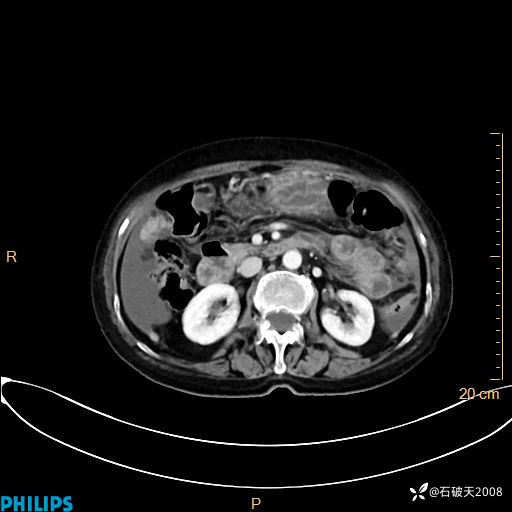

动脉期